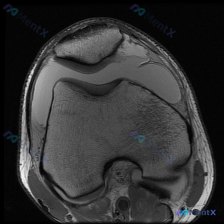

看到这个病例,整理了一下完整思路分享给大家 病例基础影像信息 本次影像为放射影像-膝盖MRI-T1序列-轴位,最初临床关注的问题是「是否存在软骨异常」。 影像学观察结果: 1. 骨骼结构:股骨远端、髌骨形态轮廓正常,骨皮质连续无骨折,骨髓信号无异常占位 2. 髌股关节软骨:髌骨及股骨滑车关节面软骨轮...